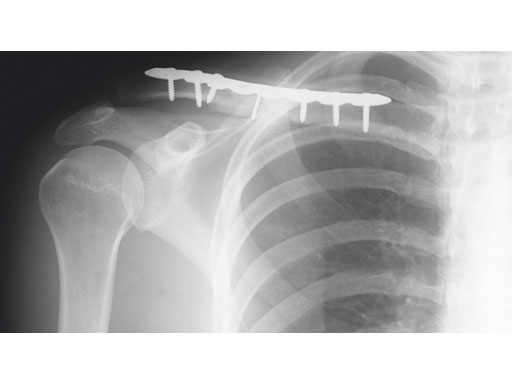

Fig 2ab Postoperative images.